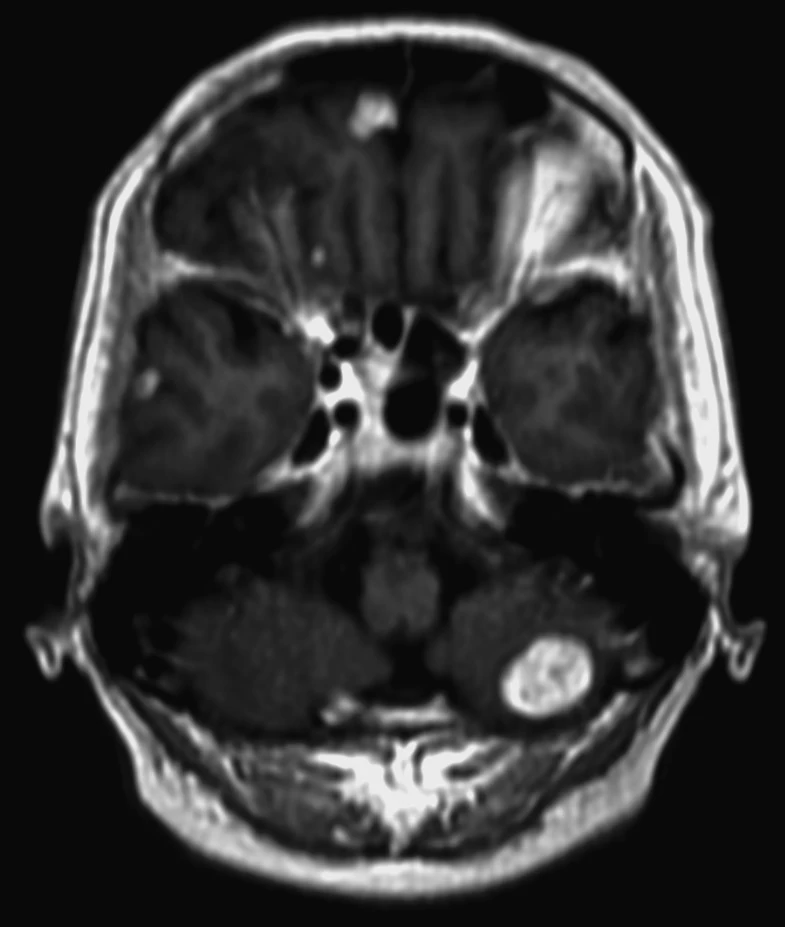

Семь менингиом и метастаз (рака молочной железы).

Четко видно, как по строению отличаются доброкачественные опухоли от злокачественных.

Первые яркие, четкие, шаровидные/полушаровидные, видно прикрепление широким основанием к костям, даже у самой мелкой.

А метастаз неровный, неяркий, нечеткий, неровный, из-за некроза, инвазии в мозг и перифокального отека.

Смотрим и запоминаем!